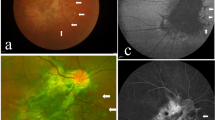

Immunohistochemical studies were carried out to further characterize the rosettes (Figs. 3, 4). Most of the rosettes appeared to consist of two concentric zones recapitulating the outer and inner nuclear layers of the normal retina. However, the rosettes were inside-out compared to the normal retina in that the outer nuclear layer was more central to the inner nuclear layer. The lumens of the rosettes were often lined by an outer-limiting membrane (short arrows in Figs. 3, 5). The majority of cells comprising the central-nuclear zone of the rosettes were positive for rod opsin (Fig. 3A). Cells in the peripheral zone were negative (asterisk in Fig. 3A). Interphotoreceptor retinoid-binding protein (IRBP), a protein normally secreted by rod and cone photoreceptors [29], was found in the luminal wall of the rosettes inside or central to the outer-limiting membrane (arrow, Fig. 3B). Immunohistochemical localization of cellular retinaldehyde-binding protein (CRALBP), a retinoid binding protein normally expressed by Müller glia, is shown in Fig. 3C. Cells with Müller cell differentiation expressed CRALBP, and showed positive radial processes abruptly ending at the outer-limiting membrane of the rosette lumen (Fig. 3C).

Immunoperoxidase localization of photoreceptor and Müller cell markers in the rosettes: A) The majority of cells comprising the central zone of the rosettes were positive for rod opsin. Cells in the peripheral zone were negative (asterisk). B) interphotoreceptor retinoid-binding protein (IRBP), which is normally secreted by photoreceptors, was restricted to the peripheral lumen of the rosette inside of the external-limiting membrane (arrow). C) Occasional cells showed Müller cell differentiation expressing cellular retinaldehyde-binding protein (CRALBP) positive radial processes that abruptly end at the external limiting membrane. Sections treated with non-immune serum showed no immunospecific reactivity (data not illustrated). Arrows in each panel indicate the position of the external-limiting membrane.

Immunoperoxidase localization of sonic hedgehog (Shh) in the normal human infant retina, and dysplastic retina. A) Ganglion cell layer from a region of normal retina of an infant with retinoblastoma. Shh is localized in the ganglion cell soma as punctate cytoplasmic staining (arrows). Shh was not detected in other regions of the retina, or in sections similarly treated with non-immune serum (data not illustrated). B) Region of normally laminated retina from the present case showed cytoplasmic shh in neurons residing in the inner nuclear layer (arrows). C) The region comprising dysplastic rosettes did not stain for Shh. Outer nuclear layer (ONL), outer plexiform layer (OPL), inner nuclear layer (INL), inner plexiform layer (IPL), and ganglion cell layer (GCL).

Comparison of dysplastic rosettes to the neoplastic rosette of retinoblastoma. A) Rosette from area of dysplastic retina in the present case.B) Flexner-Wintersteiner rosette from a case of retinoblastoma. Short arrows, external limiting membrane; long arrow in A, possible cone nuclei; asterisk, possible rod nucleus.

In view of the central role of Hedgehog signaling in the pathogenesis of holoprosencephaly and cyclopia in particular, we wanted to define the distribution of Sonic Hedgehog (Shh) in the retina of the present case. As a positive control, we used normal human retinas from the eyes of infants enucleated for retinoblastoma. In these retinas, Shh could be identified in the retinal-ganglion cells, and in some of the neurons residing in the inner zone of the inner nuclear layer. In Fig. 4A, which corresponds to a region of normal retina from a child treated surgically for retinoblastoma, ganglion-cell Shh expression appears as punctate cytoplasmic staining. A similar staining pattern could be identified in regions of normally laminated retina in the present case (Fig. 4B). In contrast, wherever retinal rosettes were present, Shh staining was absent (Fig. 4C). The normally laminated retina provides an internal positive control indicating that the absence of Shh staining in the rosettes was not a technical artifact.

Figure 5 compares the structure of a rosette from the dysplastic retina with a typical Flexner-Wintersteiner rosette characteristic of retinoblastoma. Both rosettes contain an outer limiting membrane (short arrow) lining a central lumen. In contrast to the neoplastic rosette of Flexner-Wintersteiner rosette, the rosettes of the dysplastic retina contain multiple cell types as was shown above by immunoperoxidase staining, and even here in this hematoxylin & eosin stained section where the long arrow in panel A identifies a probable cone cell nucleus among numerous rod cell nuclei (asterisk). Furthermore, the rosettes in retinoblastoma are typically positive for cone opsin, and negative for rod opsin [30]. The dysplastic rosettes show the opposite pattern expressing mainly rod opsin. Finally, Müller cell differentiation is not observed in the rosettes of retinoblastoma from surgical specimens [30].